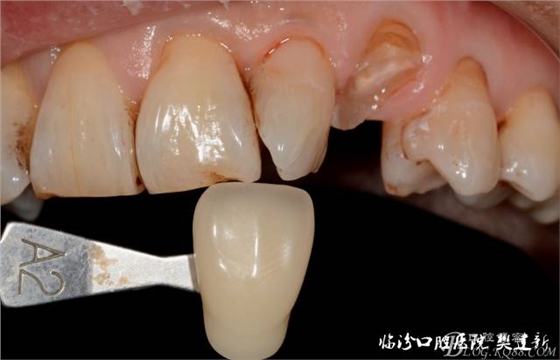

圖4修復(fù)前選色: